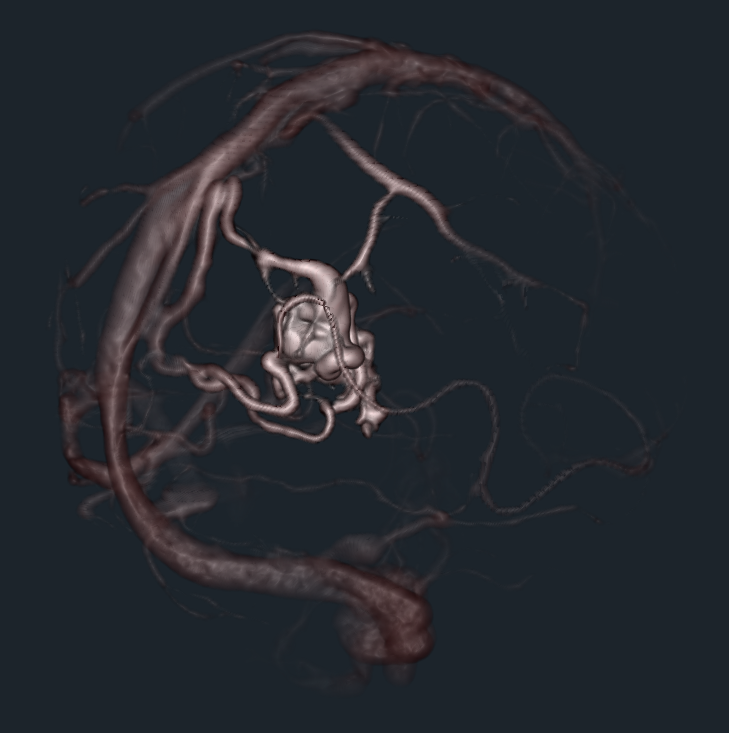

- Replicate the US heart rendering of Philips machine with data from Matt Joley.

- Provided a proof of concept (python script) for dynamic shader editing in Slicer (see image, video and link to script below)

Proof of concept

Result

Illustrations

| Philips 3D US | Chroma-depth in PRISM | Depth peeling in PRISM |

|---|---|---|

|

|

|

| Edge enhancement in PRISM | Decluttering in PRISM | Volume carving in PRISM |

|---|---|---|

|

|

|

| Blood flow animation in PRISM | ||

|---|---|---|

|